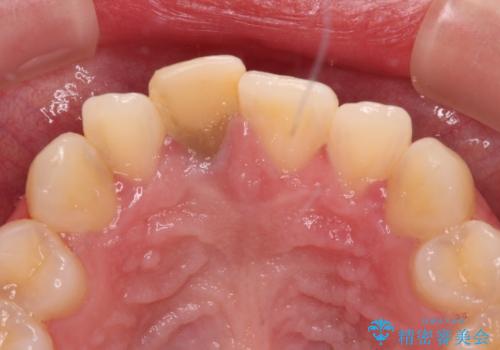

- 虫歯により神経を取り除いた前歯の変色が気になるとのことで来院された患者様です。

レントゲン写真より、歯根の炎症が認められなかったため、ファイバーコアによる土台築製後、オーダーメイドタイプのオールセラミッククラウンにて補綴することとしました。